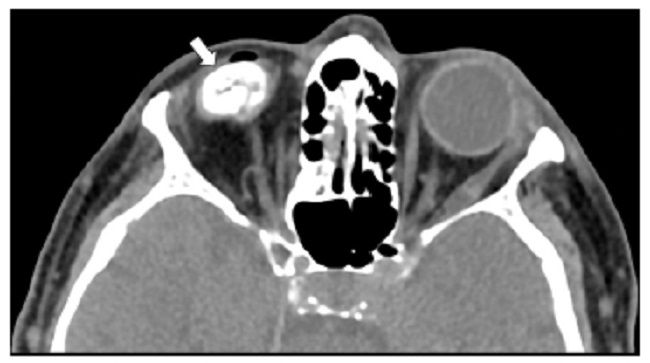

La mayoría de los cuerpos extraños en el trauma ocular son inorgánicos, como el metal y el vidrio. Los orgánicos, como la madera, son más difíciles de valorar y generan mayor respuesta inflamatoria e infecciones graves. En la TC los cuerpos extraños hiperdensos como el metal, el vidrio y el plástico se pueden identificar desde 1 mm de diámetro. Los cuerpos extraños metálicos tienen un hallazgo característico en la TC y es el destello (Fig. 11). Los cuerpos extraños de madera son más difíciles de identificar, debido a que son similares al aire en la fase aguda. Sin embargo, su forma geométrica y la medición de su atenuación ayudan al diagnóstico de cuerpos extraños de madera por TC, ya que inicialmente tienen atenuación de -100 a -200 UH (Fig. 12), la cual incrementa con el paso del tiempo debido a la acumulación de líquido. El aire presenta atenuación de alrededor de -1.000 UH. La TC tiene sensibilidad cercana al 100%, que varía según la localización y características del cuerpo extraño. La RM puede valorar el globo ocular y demostrar cambios inflamatorios asociados al cuerpo extraño cuando este no se identifica por TC. Sin embargo, está contraindicada en los cuerpos extraños intraoculares metálicos1,6.